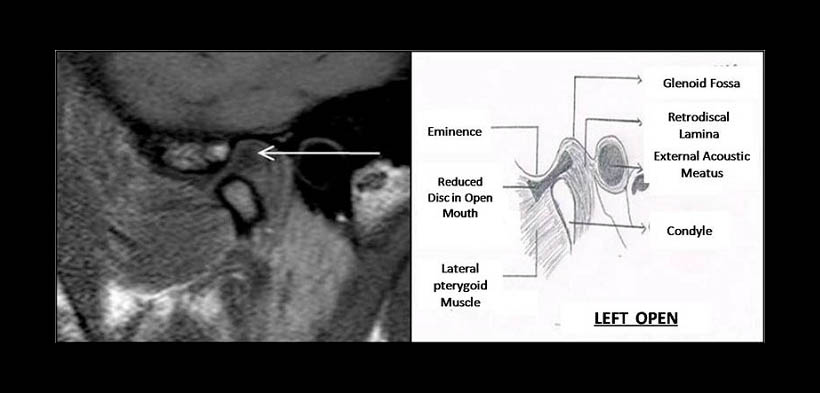

Fig. 4. DESPLAZAMIENTO DISCAL ANTERIOR CON REDUCCIÓN EN BOCA ABIERTA. Resonancia magnética de un paciente en boca abierta. Se muestra la reducción del disco a una adecuada posición y relación del disco articular con respecto al cóndilo mandibular y la eminencia articular del hueso temporal.

Fig. 6. DESPLAZAMIENTO DISCAL ANTERIOR SIN REDUCCIÓN EN BOCA ABIERTA. Resonancia magnética de un paciente en boca abierta. Se muestra que el disco articular permanece en la posición anterior con respecto al cóndilo mandibular y la cavidad glenoidea del hueso temporal.